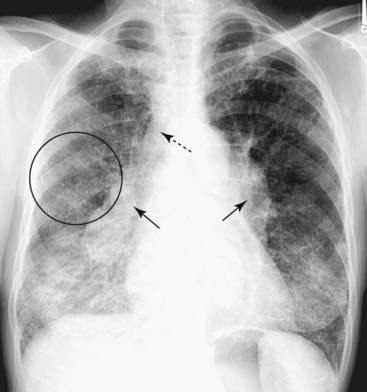

Figure 3-2 Right lower lobe pneumonia.

An area of increased opacification is in the right midlung field (solid black arrow) that has indistinct margins (solid white arrow) characteristic of airspace disease. The minor fissure (dotted black arrow) appears to bisect the disease, locating this pneumonia in the superior segment of the right lower lobe. The right heart border and the right hemidiaphragm are still visible because the disease is not in anatomical contact with either of those structures.